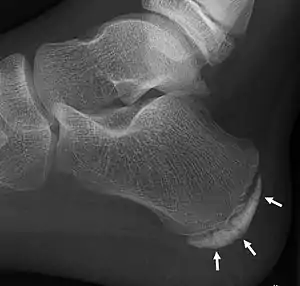

X-ray of the foot of an 11-year-old child,showing sclerosis and fragmentation of the calcaneal apophysis. This is a sign of low sensitivity and specificity of Sever's disease, because those with Sever's disease may not have it, and this appearance is also present in feet without pain.

Children with calcaneal apophysitis commonly complain of pain at the back of the heel. This pain increases with jumping and some running sports. Sometimes, the pain makes children limp and may result in poor sports performance or them not wanting to participate in some sports. The back of the heel is never swollen or red, unless there has been shoe rubbing. When the back of the heel is squeezed from the inside and outside, children with calcaneal apophysitis will report pain. Foot radiographs are not needed to diagnose calcaneal apophysitis as the growth plate can look similar with or without pain. Health professionals should only refer for imaging when the symptoms don't match with the usual presentation or there has been an injury that has resulted in heel pain. Therefore, the diagnosis of Sever's disease is primarily from history and physical assessment.[5]